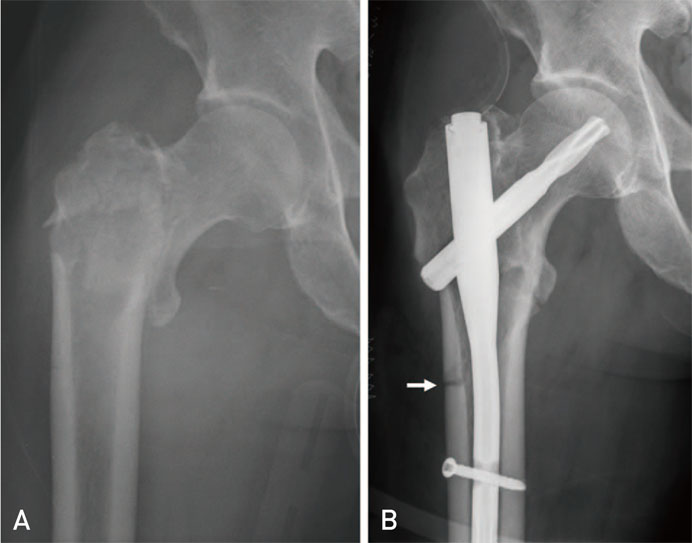

کی میتوانم مرخص شوم و چه مراقبتیهایی در طول بستری باید رعایت کنم؟ به دلیل استفاده از نیل در عمل شما، ترخیص طی حداکثر دو روز بعد از عمل انجام...